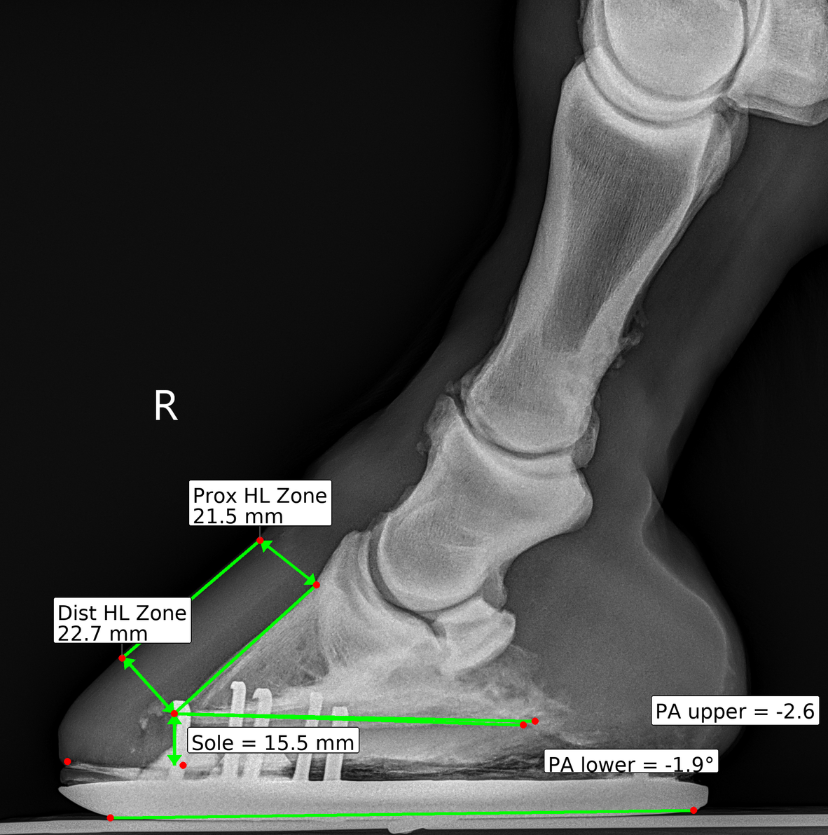

Hoof radiographs only help when both the veterinarian and the farrier can clearly see and discuss the findings. DigiHoof presents measurements and overlays in a format farriers understand and trust — improving collaboration for the horse's benefit.

Consistent overlays and measurements across visits make real comparison possible. Track hoof balance changes, sole depth progression, and alignment over time with standardized reports that speak the same language every visit.

Machine learning helps normalize landmark placement and measurements while preserving the veterinarian's clinical judgment.